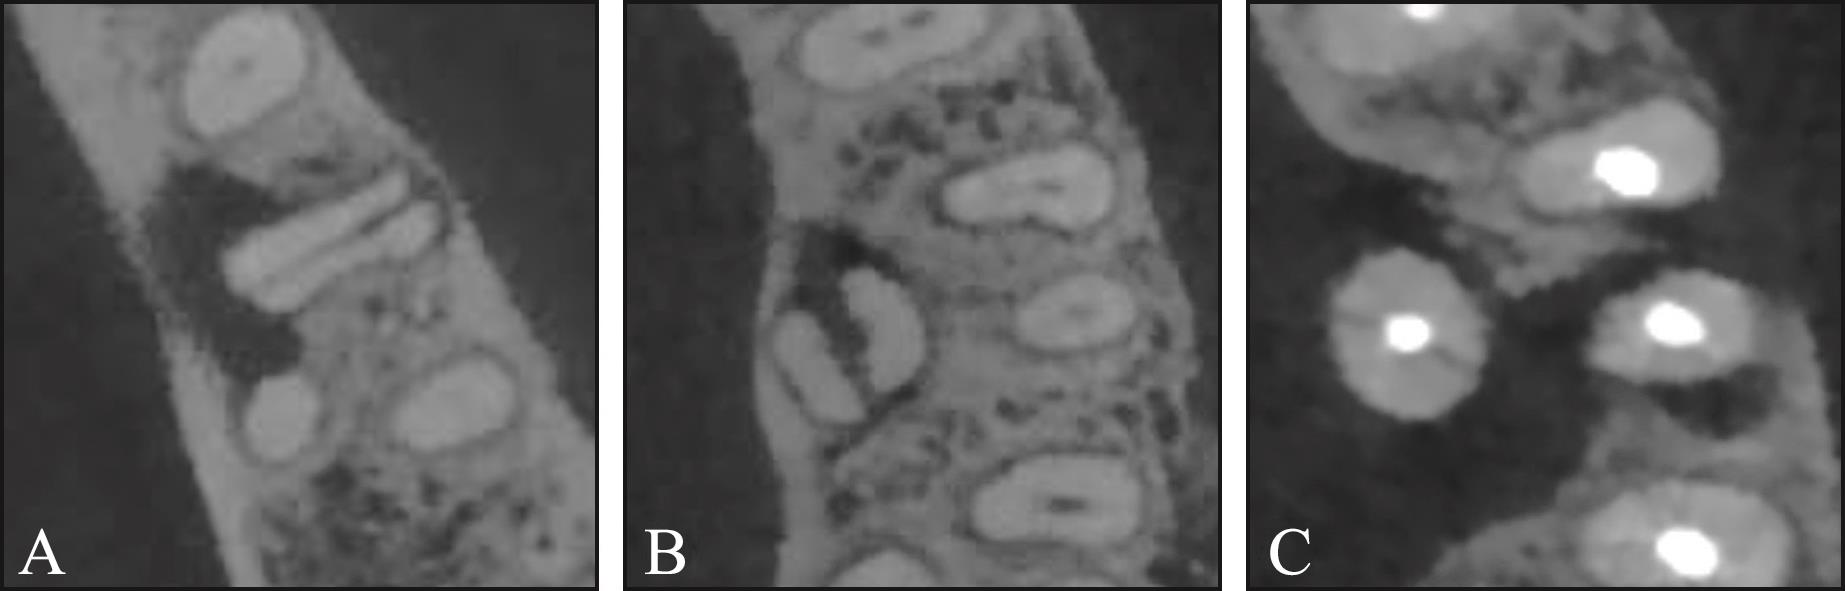

目的 探究根管治疗与非根管治疗根折后牙的临床及锥形束CT(CBCT)特征是否存在差异。 方法 回顾性收集CBCT检查发现的305例患者的340颗根折后牙,根据根折牙是否行根管治疗分为根管治疗牙和非根管治疗牙。记录根折患者的年龄和性别,在CBCT图像上评估根折发生的牙位、牙根位、根折类型(纵折、横折、斜折、不规则折)、牙根纵折方向、横折线位置及根折线周围骨吸收情况。 结果 1)非根管治疗与根管治疗根折的牙位差异有统计学意义(P=0.028)。二者根折的牙位均以上颌磨牙和下颌磨牙为主,但根管治疗牙前磨牙的发生比例(27.2%)高于非根管治疗牙(14.2%)。2)非根管治疗与根管治疗根折的牙根位差异有统计学意义(P=0.037),最常见牙根位均是下颌磨牙近中根(发生率分别为36.4%、32.2%),但排名第二的牙根位分别是上颌磨牙腭根(23.0%)、上颌前磨牙牙根(20.3%)。3)非根管治疗与根管治疗根折牙折裂类型的差异有统计学意义(P<0.001)。非根管治疗牙纵折占比为43.6%,而根管治疗牙纵折占比高达75.6%。4)非根管治疗与根管治疗纵折牙根纵折方向的差异无统计学意义(P=0.58),均以颊舌向为主(86.0%、84.1%)。5)非根管治疗与根管治疗牙横折发生位置的差异无统计学意义(P=0.132),均以根颈1/3区最常见。6)非根管治疗与根管治疗根折折裂线周围骨吸收的差异有统计学意义(P<0.001)。59.0%的非根管治疗根折牙折裂线周围有骨吸收,而根管治疗根折牙中91.8%折裂线周围有骨吸收。 结论 非根管治疗与根管治疗根折牙在临床和CBCT特征上均存在差异,非根管治疗根折牙更加复杂多变的特征表明复杂的咬合因素在根折发生中所起的作用,而根管治疗根折牙更高的一致性表明其根折发生可能与根管治疗对牙齿的结构改变有关。

Objective This study aimed to investigate the clinical and cone beam computed tomography (CBCT) characteristics of root fractures in endodontically versus nonendodontically treated posterior teeth. Methods A total of 340 posterior teeth from 305 patients were retrospectively collected. The fractured teeth were divided into endodontically treated (ET) teeth and nonendodontically treated (NET) teeth. The clinical information (age and gender of patients) was recorded. The type of fractured tooth, fractured root, orientation of fracture lines (vertical, horizontal, oblique, and irregular), direction of vertical fracture lines, location of horizontal root fractures, and bone resorption around fractured roots were evaluated and recorded based on CBCT images. Results 1) The distribution of teeth was significantly different between NET and ET teeth (P=0.028). Root fractures predominantly occurred in mandibular and maxillary molars. However, the proportion of premolars was significantly higher in ET teeth (27.2%) than in NET teeth (14.2%). 2) We observed a significant difference in root distribution between NET roots and ET roots (P=0.037). The mesial roots of mandibular molars were the most common fractured roots in NET and ET roots (36.4% in NET roots and 32.2% in ET roots); however, the second most common roots were the palatal roots of maxillary molars in NET roots (23.0%) and the maxillary premolar roots in ET roots (20.3%). 3) A statistically significant difference in the orientation of root fractures was observed between the two groups (P<0.001). Vertical root fractures accounted for only 43.6% of all root fractures in NET root fractures, whereas they accounted for 75.6% in ET root fractures. 4) For vertical root fractures, the direction of fracture lines between NET and ET root fractures was not significantly different (P=0.58), with both types predominantly presenting as buccal-palatal fractures (86.0% and 84.1%). 5) No significant difference was observed in the location of horizontal fractures between NET and ET root fractures (P=0.132), and the most common site was the cervical third of roots. 6) Bone loss around fractured lines significantly differed between NET and ET root fractures (P<0.001). Around 59% exhibited obvious bone loss around fractured roots in NET root fractures, whereas 91.8% of fractured roots presented bone loss in ET root fractures. Conclusion The NET root fractured teeth and ET root fractured teeth presented quite different clinical and CBCT characteristics. The complex and diverse traits of NET root fractured teeth indicate the influence of multifaceted occlusal factors in their occurrence. By contrast, ET root fractured teeth demonstrate high uniformity, indicating that their occurrence may be related to the structural changes caused by endodontic treatment.